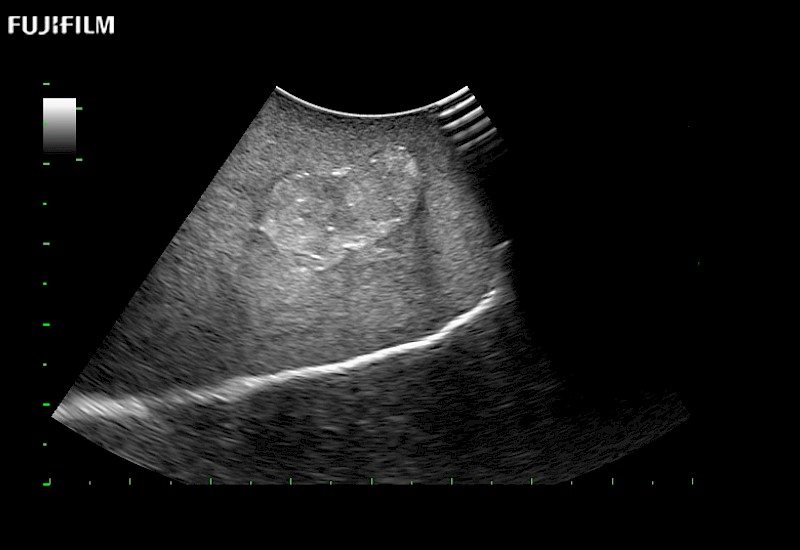

Curved array 4-way laparoscopic transducer for better visualization of targeted lesions.

Main Specifications: